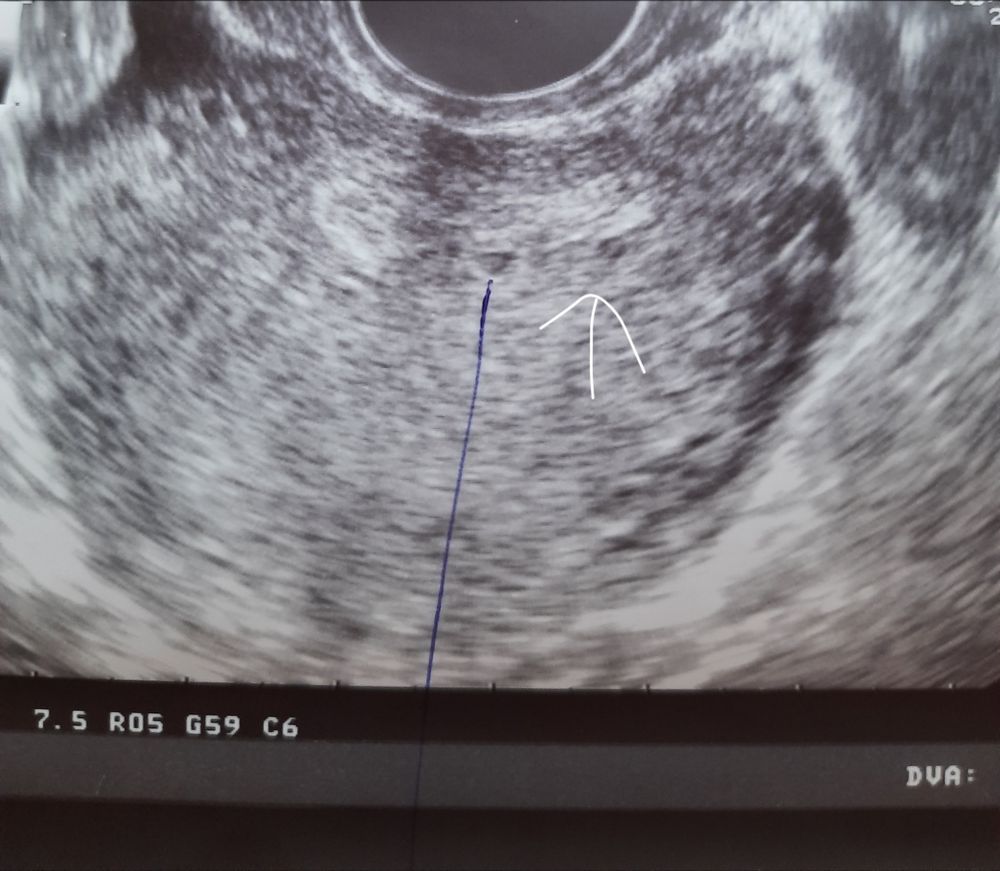

2 ПЯ?

Женевьева, один малыш у нас))второй куда то пропал😄или его вообще не было.Спасибо Господу за этого малыша🧿🙏

Совсем не исключено ))) Начинайте сдавать хгч. Там с двумя сразу много должно быть и расти бешено )

Дарья Палецких, да,хгч за 2 дня вырос с 570 до 3312😄но я внимания не обратила

Мама индахаус, ну прямо образцовый рост для близнецов ))))

Юлия , но одно ведь жёлтое тело)как тогда 2 пя?😄

Мама индахаус, на таком маленьком сроке много что можно не рассмотреть, вы выше написали об огромном приросте хгч, это вполне себе хороший признак двоих малышей)))) а узи попозже покажет скорее всего